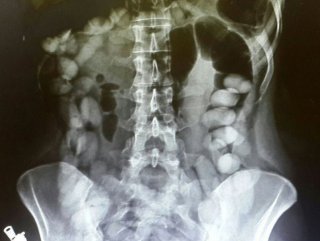

Tayland basınındaki haberlere göre, gümrük memurları x-ray cihazından geçen Suamu Nkele'nin midesinde bazı maddeler göründüğünü tespit etti.

İncelemeler sonrası midesinde 1,2 kilogram uyuşturucu madde bulunan kadının çorap ve iç çamaşırlarına da uyuşturucu yerleştirdiği ortaya çıktı. Angola'nın başkenti Luanda'dan Bangkok'a seyahat eden kadın, emniyet güçlerince gözaltına alındı.